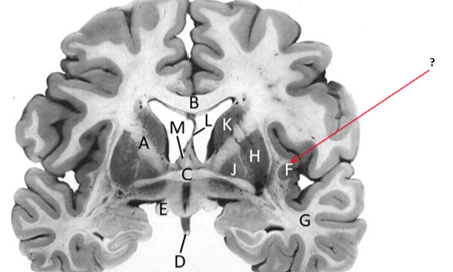

Name this and state its function.

Corpus Callosum.

Putamen.

Name this, state its function, pathways and cellular components.[5 marks]

Caudate nucleus.

Medium spiny neurons utilising GABA and some Cholinergic.

From cortex–>CN–>hippocampus, Gp and thalamus.

Septum pellucidum.

Fornix.

Anterior commissure.

Interconnects:

Infundibular stalk.

Insula.

Name this, state its function, components[2] and the difference in pathways.

Internal capsule.

Anterior limb:

Posterior limb:

Corticospinal tracts and corticopontine tracts: